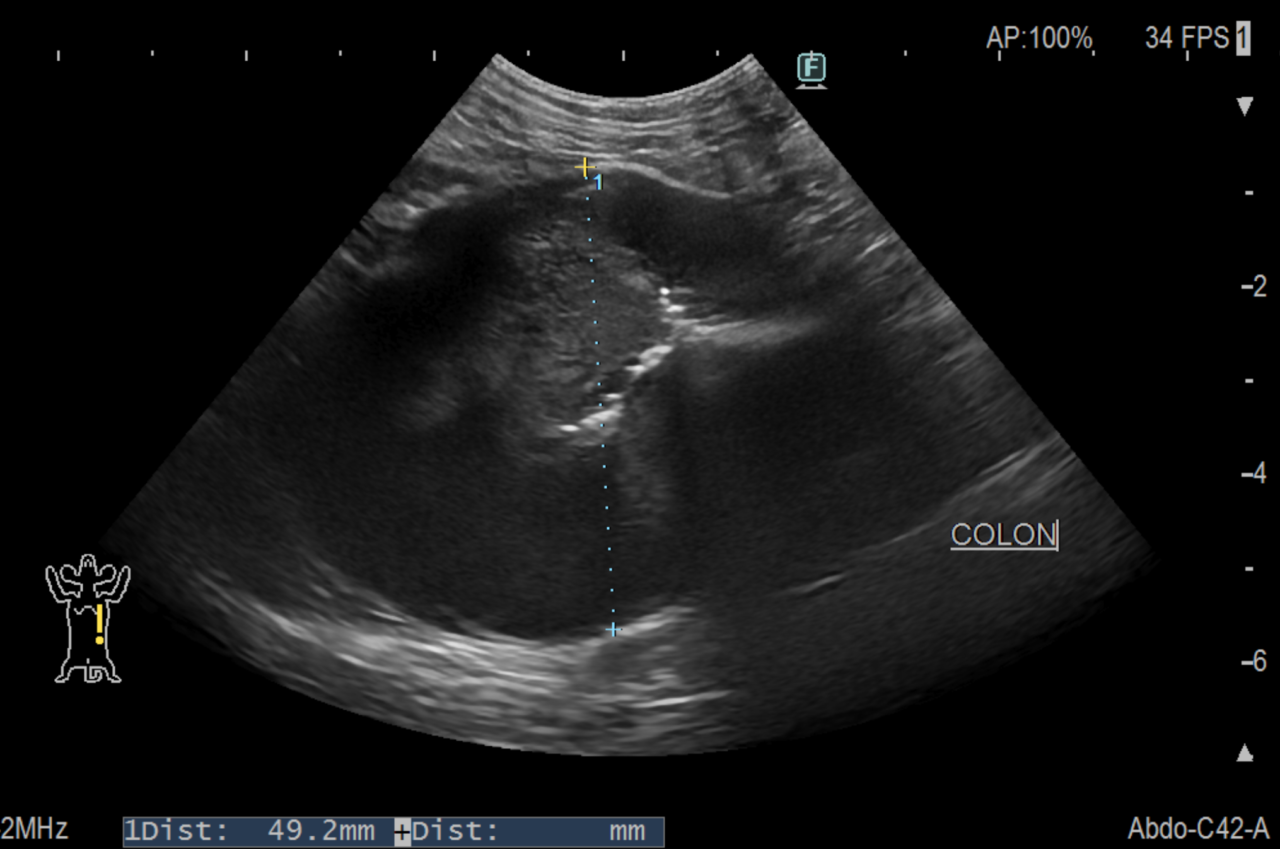

腹部エコー検査で結腸、肝臓、リンパ節が腫瘍化していることが確認され、経皮的針生検を行いました。いずれのサンプルからも肥満細胞が検出され、肥満細胞腫と診断しました。